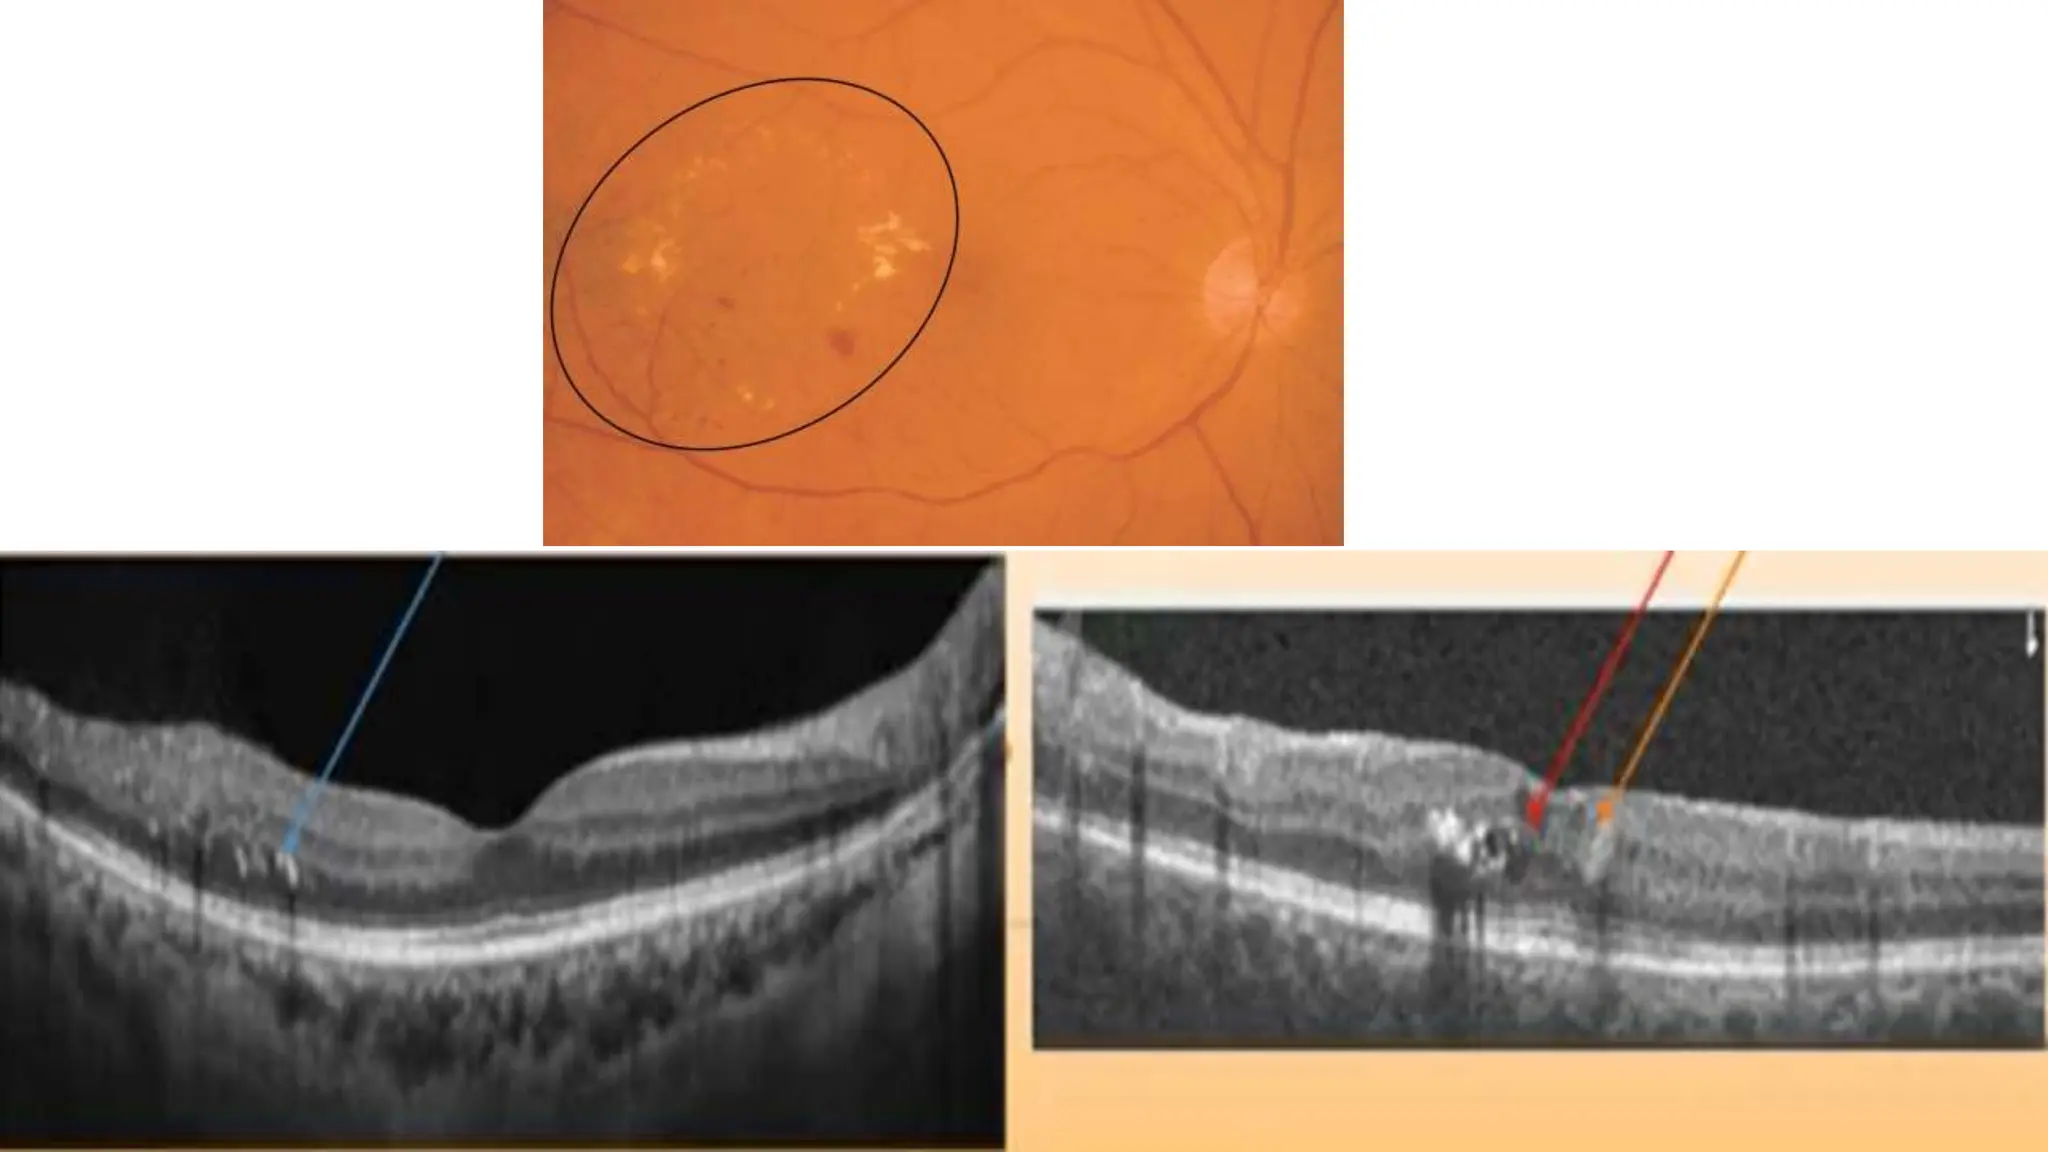

The document discusses various stages of posterior vitreous detachment (PVD) and associated ophthalmological conditions. It highlights the classification of PVD stages, including no PVD, paramacular PVD, and complete PVD, alongside related factors like traction and retinal issues. Key acronyms and terms relevant to diabetic retinopathy and retinal morphology are also mentioned.